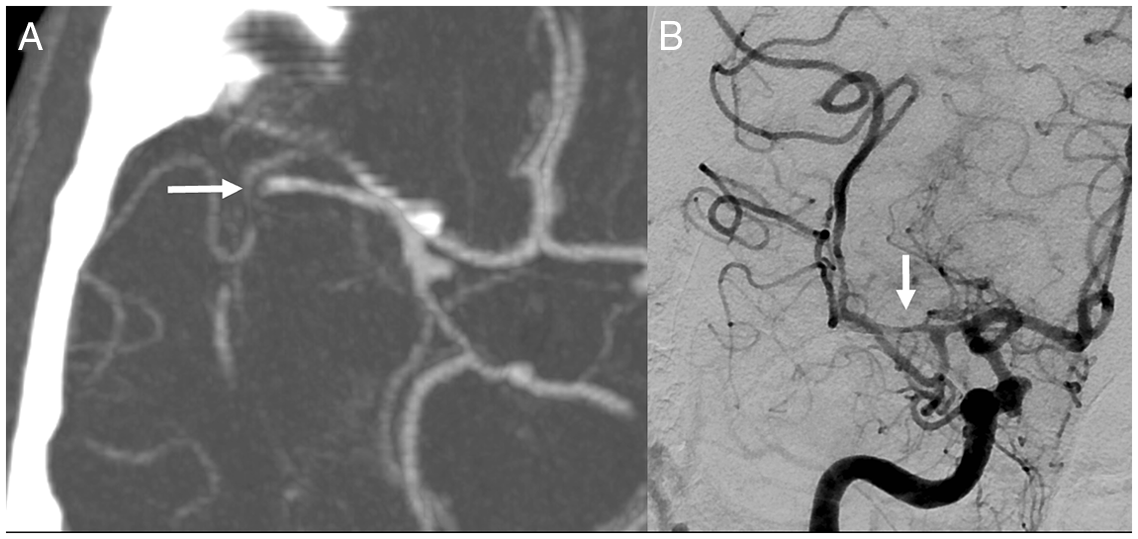

A 50-year-old man with a history of smoking and unspecified drug use suffered an acute ischemic stroke and was transferred to our stroke center for mechanical thrombectomy (MT). He had awoken with a complete right hemispheric syndrome and a right middle cerebral artery (MCA) occlusion of the M1 segment on CT angiogram (CTA) (Figure 1a). He did not receive thrombolysis at the referring center because of the unknown time of onset, although his ASPECTS was favorable (9) on baseline CT. He underwent MT with TICI 2a (Thrombolysis in cerebral infarction) recanalization after one pass with a stent retriever (Figure 1b).

Figure 1: Right middle cerebral artery occlusion and reperfusion.